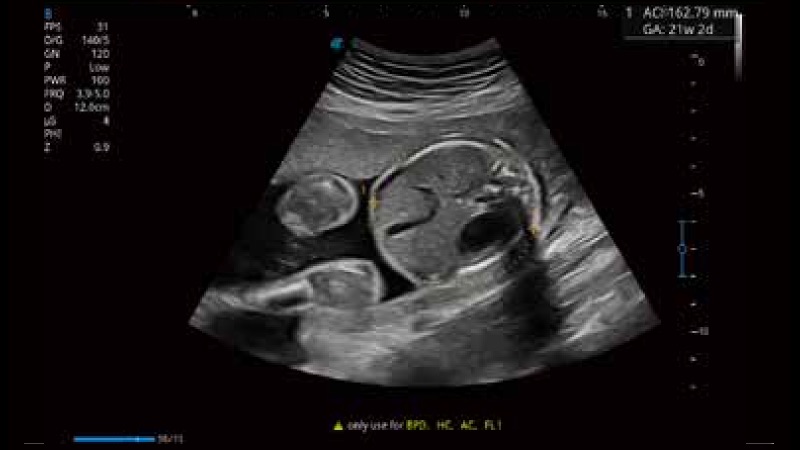

開立醫(yī)療通過不斷的技術(shù)創(chuàng)新,為大眾的生命健康提供持續(xù)關(guān)愛。P12 Plus采用全新一代超聲成像平臺,新平臺旨在將真實(shí)還原組織解剖結(jié)構(gòu)作為首要目標(biāo)。平臺采用全新集成化硬件模塊,搭載新一代芯片,系統(tǒng)性能得到大幅提升,為您的診斷提供了豐富的臨床信息。優(yōu)異的圖像表現(xiàn),豐富的探頭配置,全面的應(yīng)用功能,為您日常診斷提供了可靠的助手。

P12 Plus

彩色多普勒超聲診斷系統(tǒng)